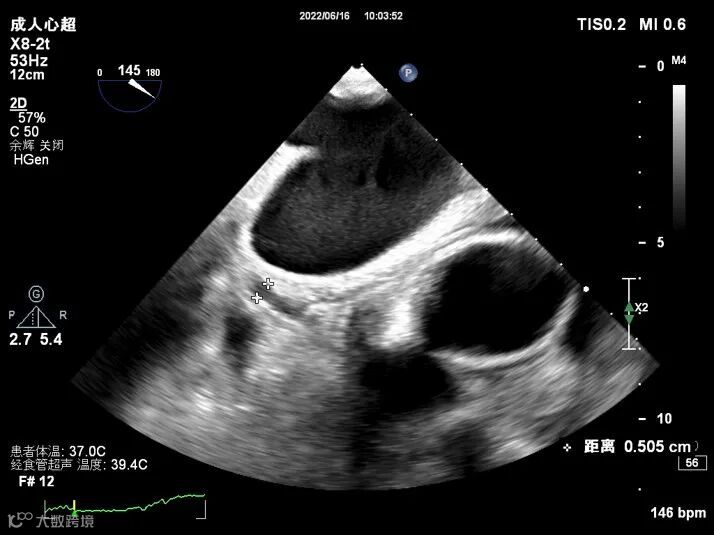

TEE图像如下:

图1:TEE示左心耳内未见异常光团回声

图5-1图5-2:二维显示回旋支内径增宽(短轴及长轴),较宽处内径约0.5cm,未见瘤样扩张,管腔内未见异常回声。